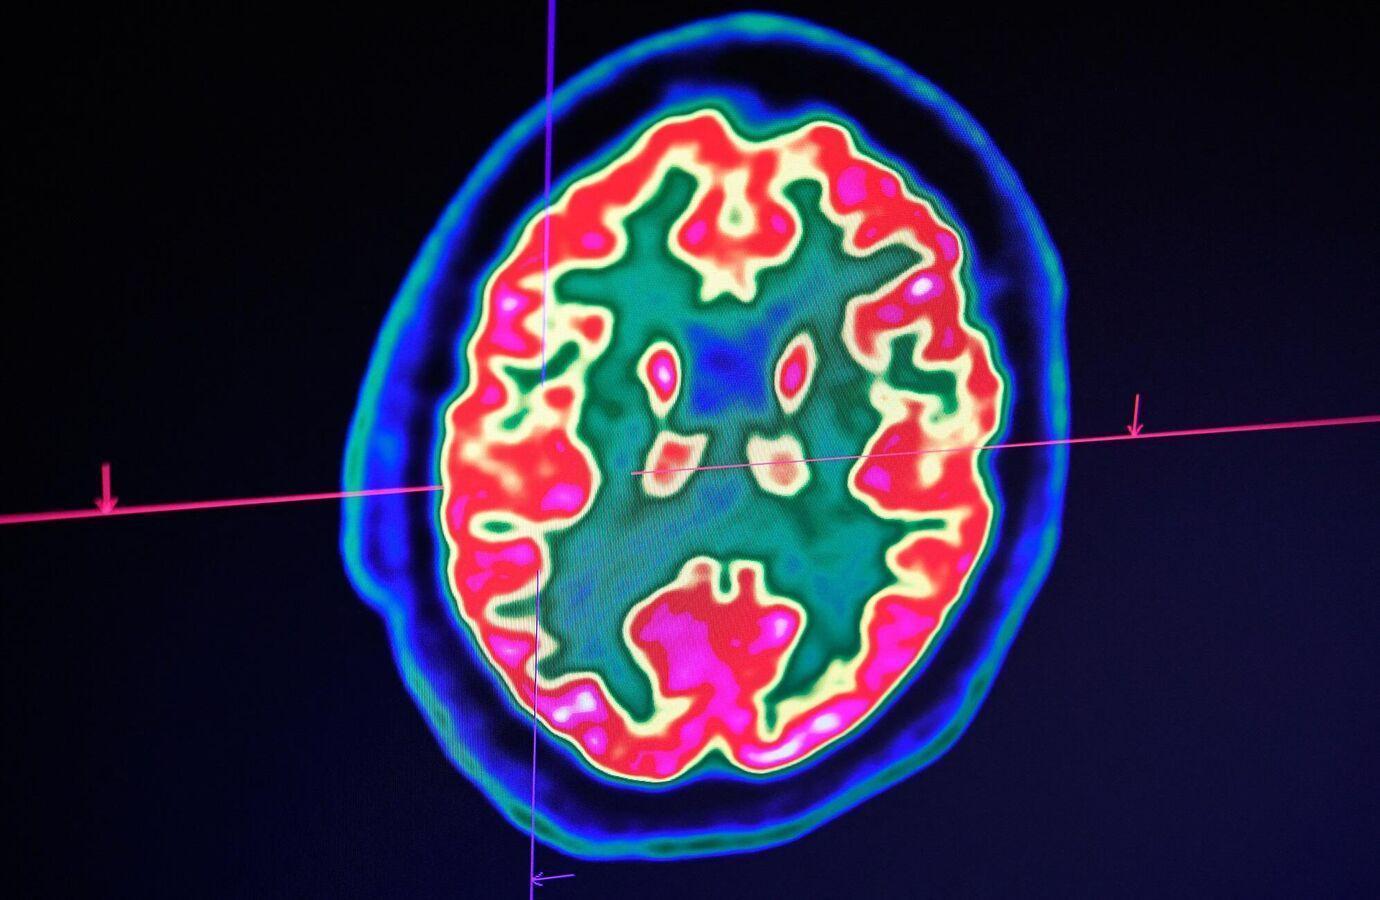

واكتشف فريق الدراسة، المنشورة في مجلة “Communications Medicine”، أنه بعد إجرائهم تحليلا شاملا لقشرة الدماغ، وجدوا أن مناطق معينة من الدماغ تشارك في تنظيم العواطف والإدراك وما إلى ذلك، تتغير مع مرور الوقت، نتيجة السكن في حي محروم من الناحية الاجتماعية والاقتصادية.

وقام الباحثون بالتحقيق في الروابط بين “مؤشر الحرمان في المنطقة” ونتائج التصوير العصبي على 4 مستويات من قشرة الدماغ لدى المشاركين، الذين خضعوا لنوعين محددين من فحص التصوير بالرنين المغناطيسي، والذي تم فحص نتائجه بعد ذلك.

ووجدت الدراسة أن انخفاض معدلات “مؤشر الحرمان في المنطقة” ارتبط بتغيرات التواصل في مناطق الدماغ المهمة من أجل التفاعل الاجتماعي، ويبدو أن تناول الأحماض الدهنية المتحولة، الناتج عن عادات الأكل السيئة، يؤثر على مناطق أخرى من الدماغ أيضا، مما يؤثر على العمليات المعرفية وتنظيم العواطف.

وعن نتائج الدراسة، تقول كبيرة مؤلفيها، الطبيبة أربانا جوبتا، وهي المدير المشارك لمركز جودمان لوسكين ومدير مركز التصوير العصبي: “وجدنا أن عيوب الحي كانت مرتبطة بالاختلافات في البنية الدقيقة لقشرة الدماغ، وارتبطت بعض هذه الاختلافات بارتفاع مؤشر كتلة الجسم، كما ارتبطت بتناول كميات كبيرة من الأحماض الدهنية المتحولة الموجودة في الوجبات السريعة المقلية”.

وأضافت جوبتا أنه على وجه التحديد، يبدو أن الدراسة تشير إلى أن مناطق الدماغ المشاركة في “المكافأة والعاطفة واكتساب المعرفة والفهم، قد تتأثر بجوانب الحرمان في الحي، التي تسهم في السمنة”.